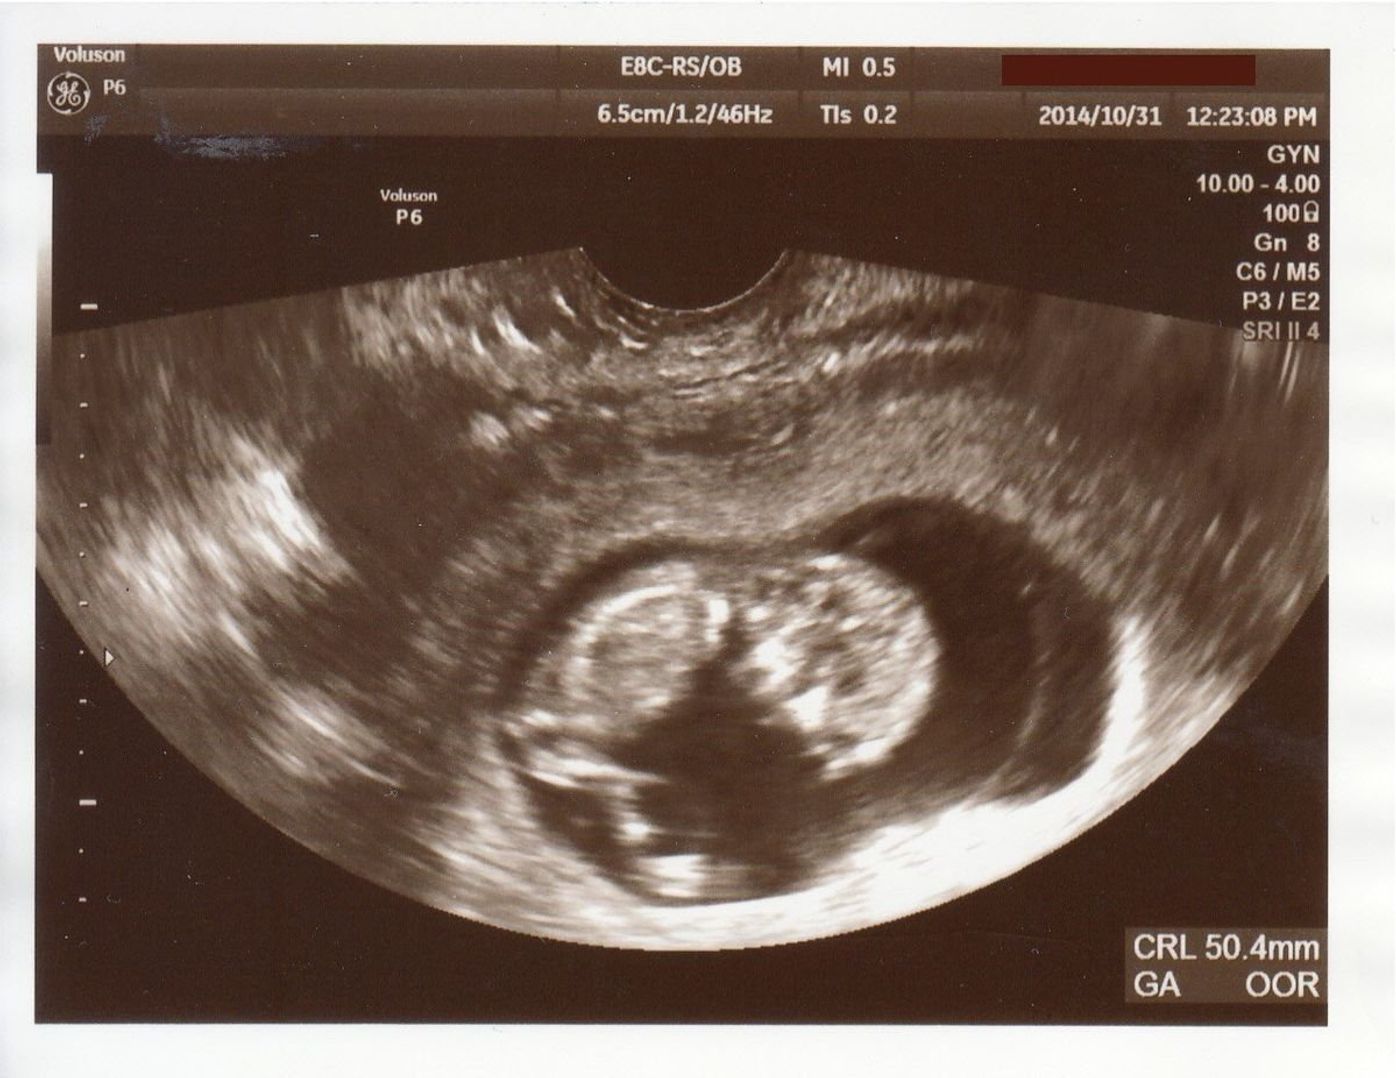

こちらのエコーは女の子ですか 男の子ですか 妊娠7ヶ月目 24 Yahoo 知恵袋

妊娠24週目 24w0d 6d のエコー写真とエピソード 妊娠7ヶ月 Cozre コズレ 子育てマガジン

妊娠7ヶ月 エコー写真でここまで分かる ついに性別判明 25歳はじめての妊娠 8 18年3月21日 エキサイトニュース 2 3

妊娠24週 7ヶ月 エコー写真での性別診断お願いします 先日7ヵ月健診に Yahoo 知恵袋